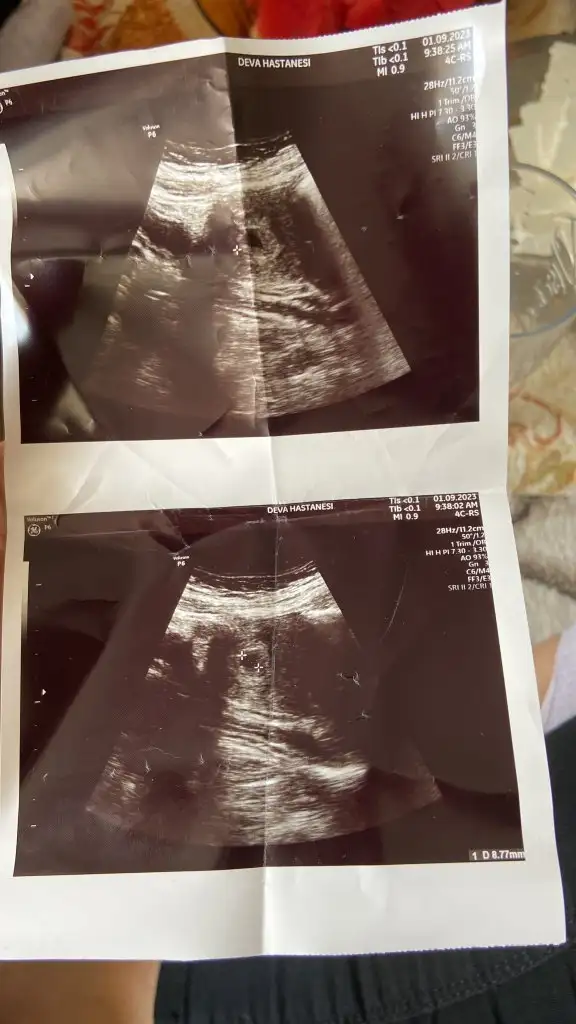

Merhaba bizede tahminde bulunur musunuz

5 hafta ile uyumlu karın usg bakar mısınız benim bebişimede